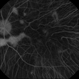

- pigment changes, choroideremia

- FA of choroideremia carrier with diffuse mottled fluorescence from pigment changes